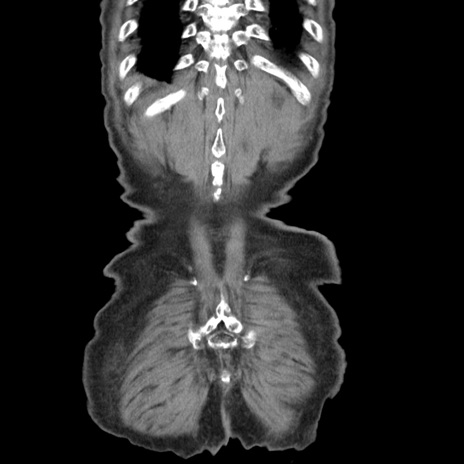

症例24(冠状断像)

症例